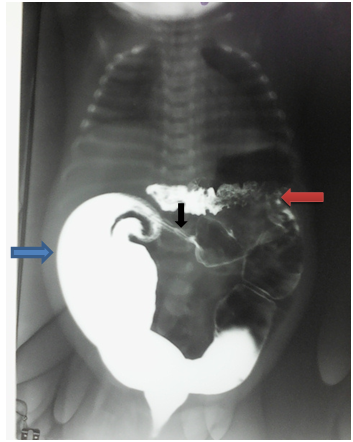

In total, it is a sub-occlusive syndrom associated with upper digestive tract malformation. We suspect the coexistence of an abnormality of the lower digestive tract. It evoked, the less likely the most likely, a irritable bowel syndrom, a gastrointestinal stenosis and Hirschsprung disease. We then carried out the following additional tests: Thorax and abdomen radiological examination without preparation showed (Figure 3): a large aeric and stercoral stasis drawing the entire colon, including the rectum, an absence of hydro-aerial level, a thickening of the intestinal walls of the recto-sigmoid region.

Figure 3 Thoraco abdominal radiological examination without preparation: significant aeric and stercoral stasis drawing the whole colonic frame (including rectum) without hydro-aerial level. Thickening of the colonic wall rectosigmoid region (green arrow).